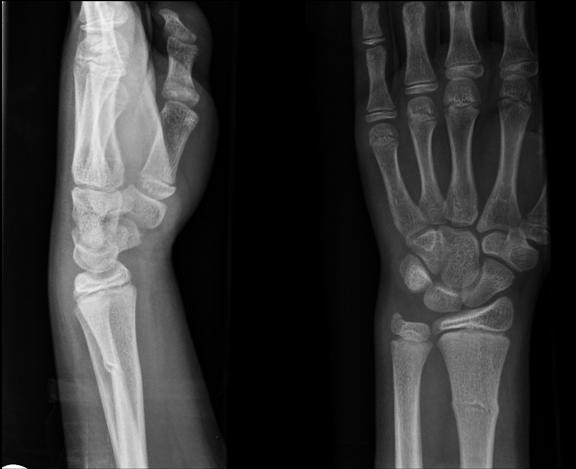

A Torus fracture, also known as a buckle fracture, is a common injury seen in children. It is a compression failure of bone.

Because the bones of children may be softer on one side, one side may buckle when stressed without affecting the other side.

Torus fractures usually occur at the junction of the metaphysis and diaphysis, especially in the distal radius.

Torus fractures are diagnosed with x-ray imaging. This injury is referred to as a torus fracture because of its similarity to the raised band around the base of a classic Greek column when viewed on x-ray.

Torus fractures are inherently stable and heal in 2-3 weeks with simple immobilization, such as casting.

Greenstick

A Greenstick fracture is an incomplete fracture of long bones that is commonly seen in children. The bone bends and cracks but does not break into pieces, largely due to the softness and flexibility of bones in children.

These fractures occur when the bone is bent and there is failure on the tensile (convex) side of the bone. This is different than in torus fractures where the concave side buckles.

The fracture line does not propagate to the concave side of the bone, but the concave side shows evidence of microscopic failure with plastic deformation.

X-ray imaging will show a mid-diaphyseal break, usually with angulation and disruption of the cortical bone on the side of the fracture.

It may be necessary to break the bone on the concave side in order to achieve reduction of the fracture because the plastic deformation recoils it back to the deformed position. Immobilization with casting for 2-3 weeks allows this fracture to heal.